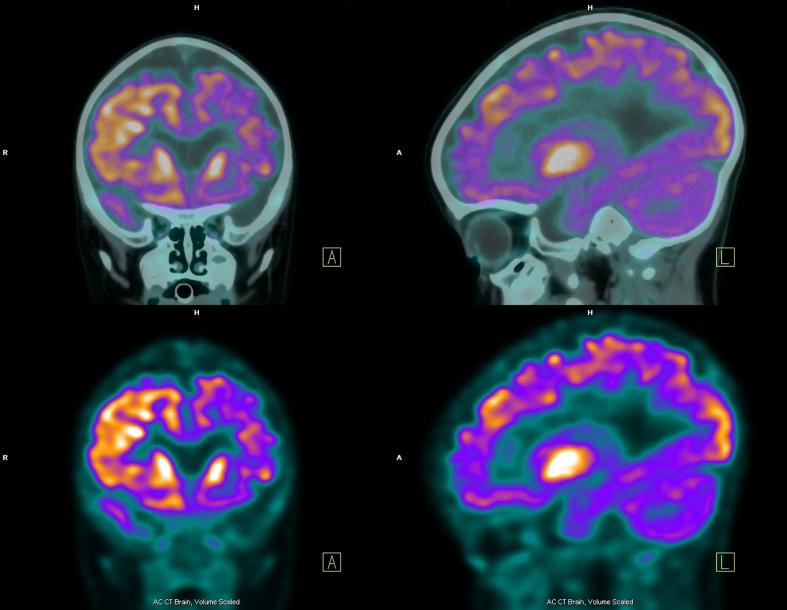

Como adelantábamos, hace referencia a estas malformaciones que han tenido lugar en la corteza cerebral durante su desarrollo. Aunque posee anomalías estructurales muy complejas, resulta complicada de detectar al realizar un escáner cerebral. Sus evidencias pueden ser tan sutiles que podrían pasar desapercibidas. Esta es la razón por la que es tan importante prestar atención a los síntomas de la displasia cortical.

Existen diferentes tipos de displasia cortical, pero su diagnóstico responde a varios factores y debe ser efectuado por un médico.